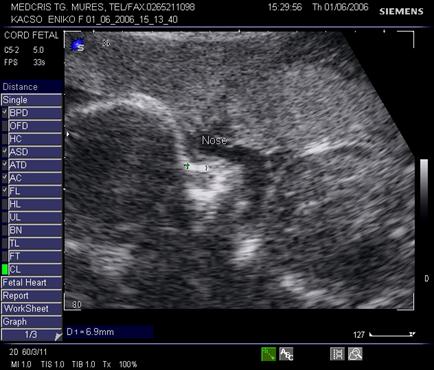

Fig. nr. 281. Acelasi fat cu anamnios si RCIU, cu os nazal relativ scurt